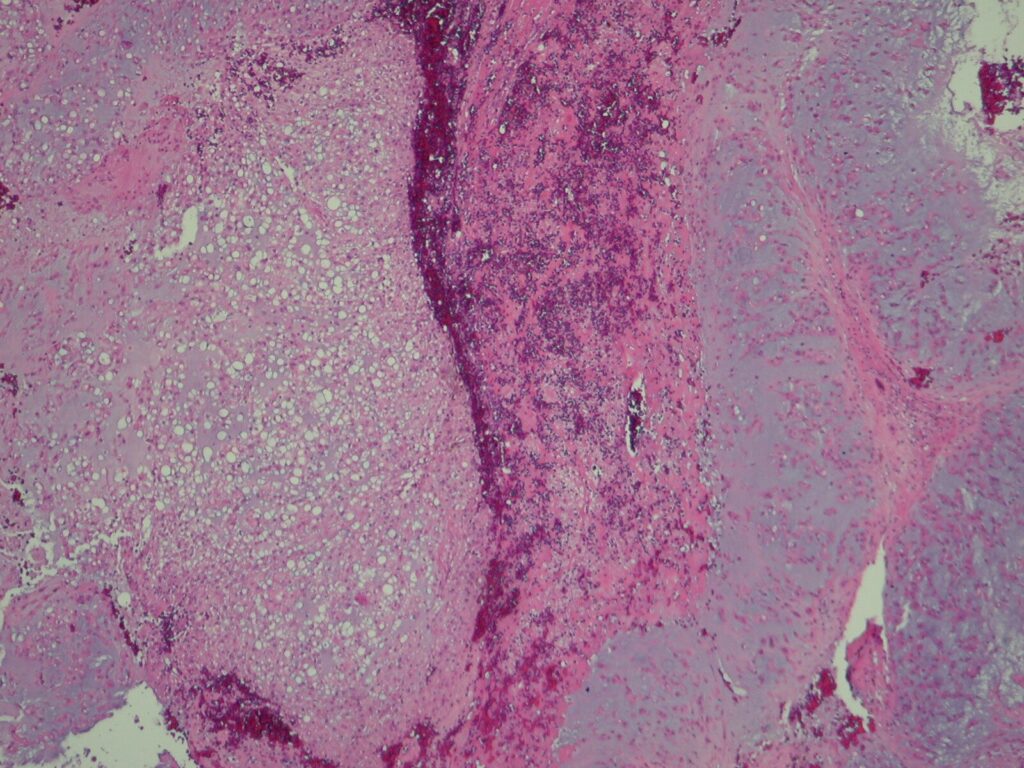

Microscopic (Fig. 13 & 14)

• Proliferation of large cells with eosinophilic cytoplasm with vacuoles (physalipherous cell)

• Nuclei are round/oval with prominent nucleolus

• Physalipherous cells are surrounded by myxoid matrix

• Lobules separated by fibrous septa

• Few nuclear polymorphism

• Few to no mitotic figures

• May exhibit cartilaginous differentiation

• Some show aggregates of microtubles in cytoplasm

• Chordomas coexpress S-100 protein (Fig. 15) and epithelial markers

Fig. 13 & 14: Microscopic pathology demonstrates hypercelularity forming lobules separated by fibrous septa. Higher magnification shows physaliferous cells that arelarge cells with bubbly cytoplasm surrounded by myxoid matrix. No mitotic figures are distinguished.